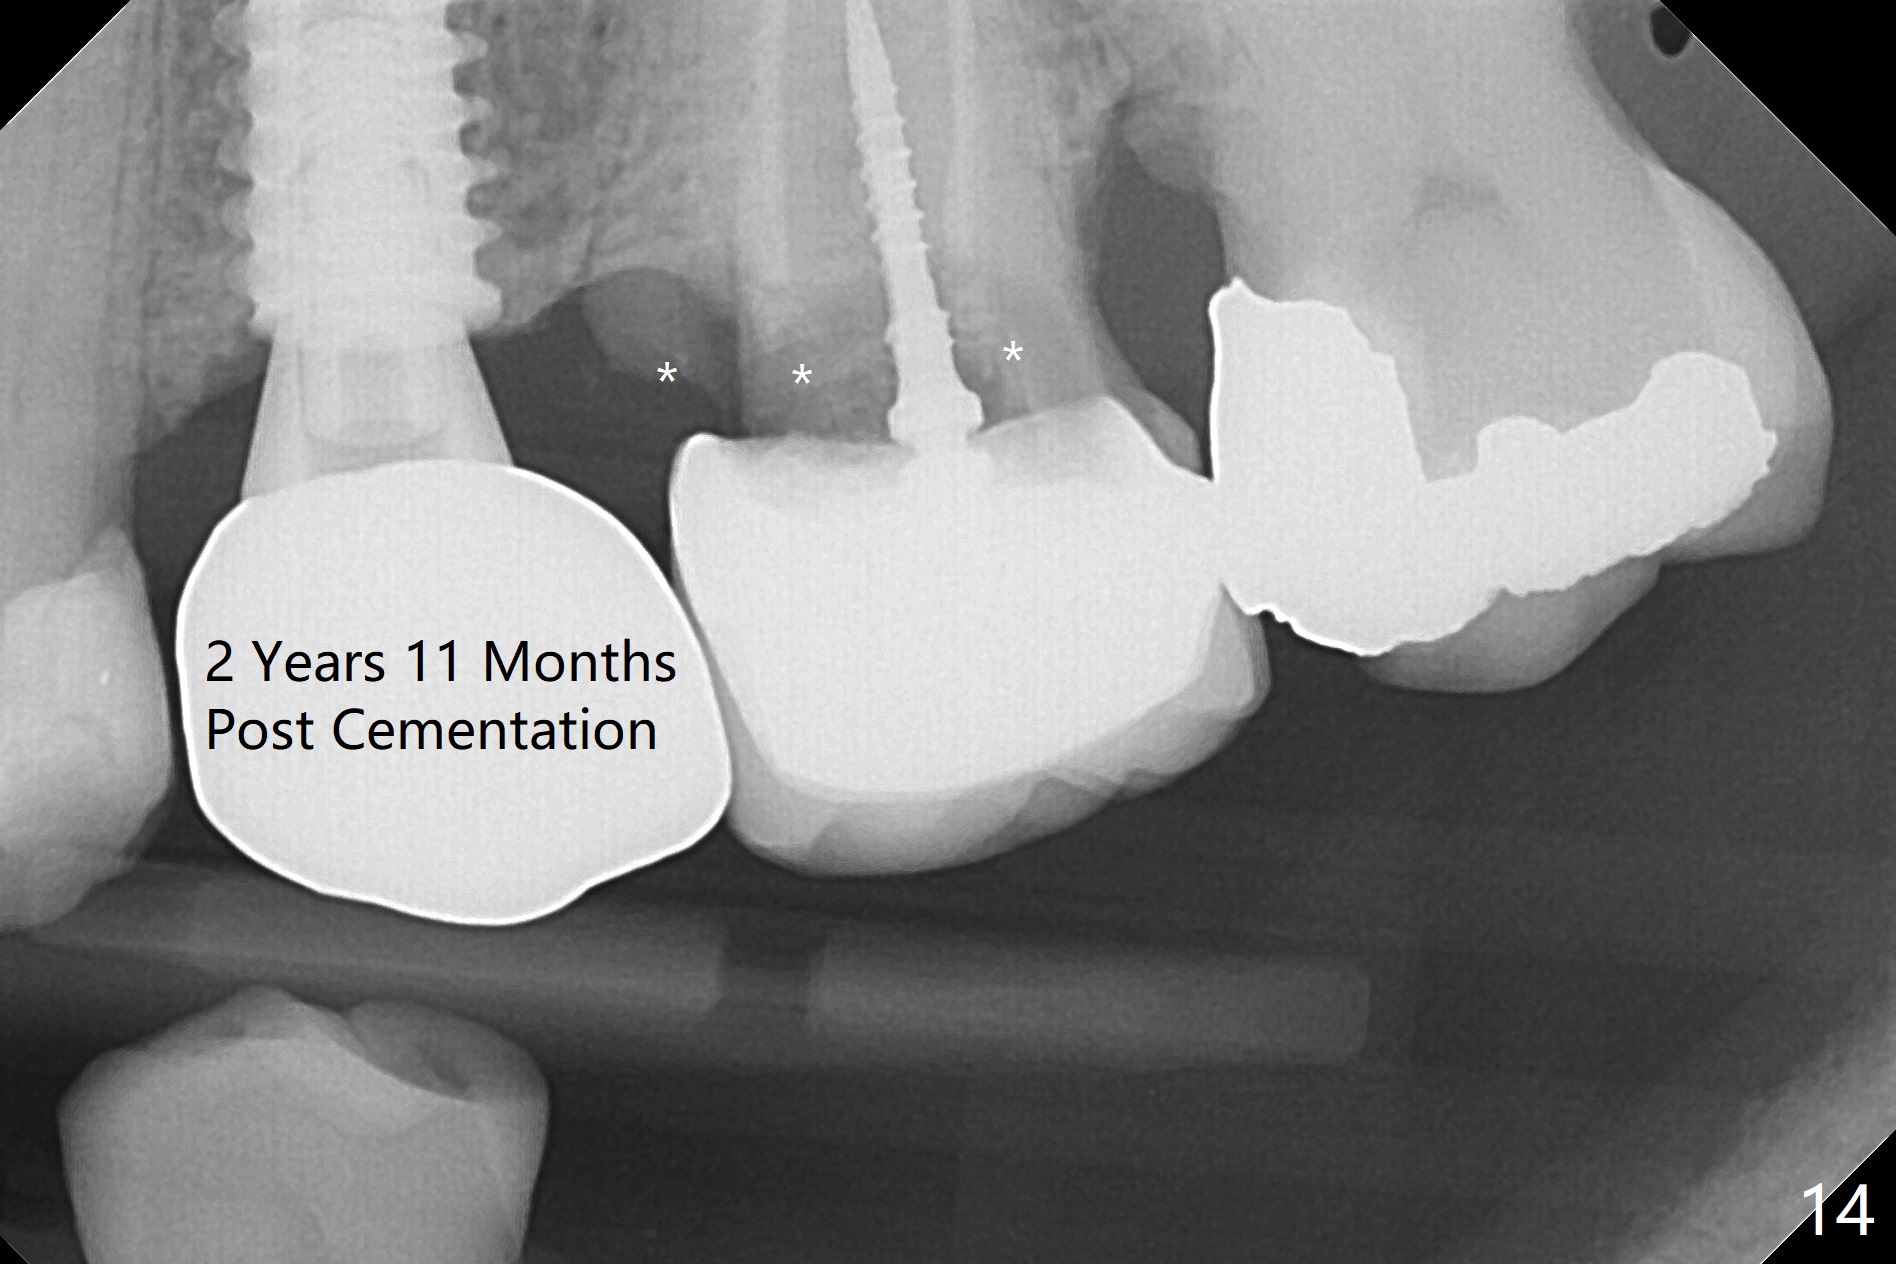

Since the apical native bone is limited at #13 after extraction, no PA is taken until a 4x11 mm dummy implant is placed after 1.6 mm and 3.3 mm drills for 13 mm (Fig.1). After using Lindamann bur to move the osteotomy distal and reusing 3.3 mm drill, the trajectory of a 4.5x11 mm IBS dummy implant improves (Fig.2,3 with low stability). When the implant is removed, the buccal portion of the socket is found to be perforated (Fig.4 P). Although the reason for the perforation is unknown, it is repaired by insertion of a piece of PRF plug, followed by allograft. #1 and 2 in Fig.4 represent the 1st and 2nd osteotomies, as shown in Fig.1 and 2, respectively. The trajectory of the final 5x13 mm implant is acceptable (Fig.5-7, different angulations), so is insertion torque (45 Ncm). After placing a 5.5x4(4) mm abutment, an immediate provisional is fabricated (Fig.8 P) with occlusal clearance (*). The interdental papillae remain in place 12 days postop (Fig.9 *). There is no sign of postop sinus infection. The provisional is loose 18 days postop; the abutment is changed to 5x4(3) mm (Fig.10). It is difficult to catch the mesial margin of the abutment for impression 4 months postop, due to poor oral hygiene and the short cuff (3 mm, Fig.11). The appointment for impression is rescheduled with emphasis on oral hygiene and no wearing the provisional for a few days prior to next appointment. Bone has grown into the space between the 1st and 2nd threads 5 months post cementation (Fig.12) and the bone is normal, solid and dense 2 years 11 months post cementation (Fig.13 >). There is mesial open margin of the tooth #14 (Fig.13,14 *).